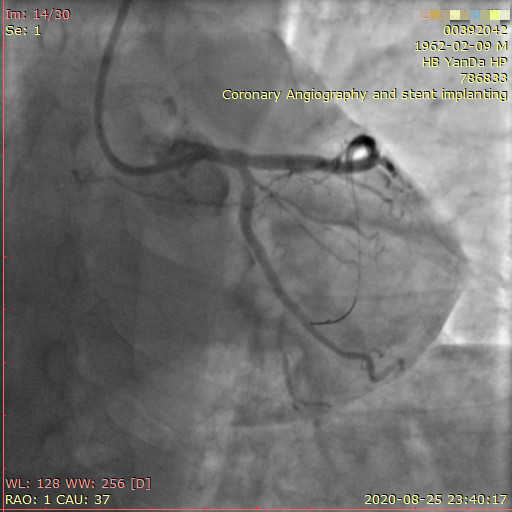

李先生蜘蛛位術前影像

李先生蜘蛛位術后影像